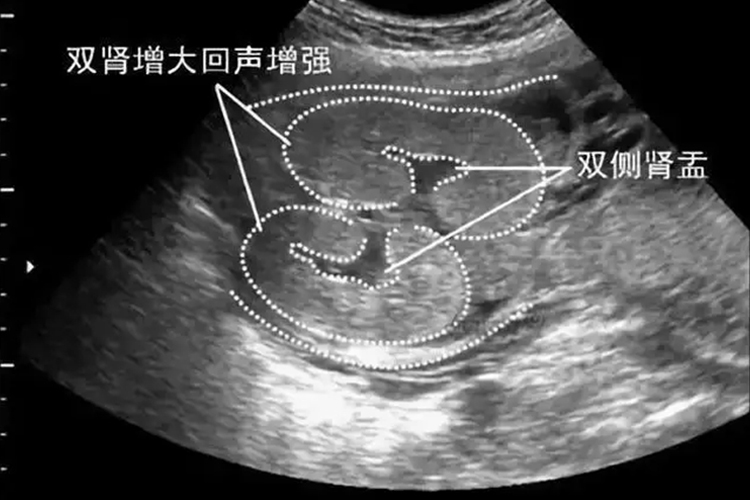

大排畸是在妊娠20-24周通过超声检查,判断胎儿是否存在脊柱椎弓间距增宽、软腭裂、心脏增宽等发育畸形情况。

大排畸通常在妊娠20-24周时进行的胎儿系统超声检查,筛查胎儿结构畸形。正常情况下胎儿心、脑、肾、膀胱、胃、上唇、四肢骨、脊柱、腹壁等均正常。当出现侧脑室增宽、脊柱椎弓间距增宽、软腭裂、双肾增大、心脏增宽、裂腹畸形伴肠管外翻等异常情况时,多提示胎儿发育异常。